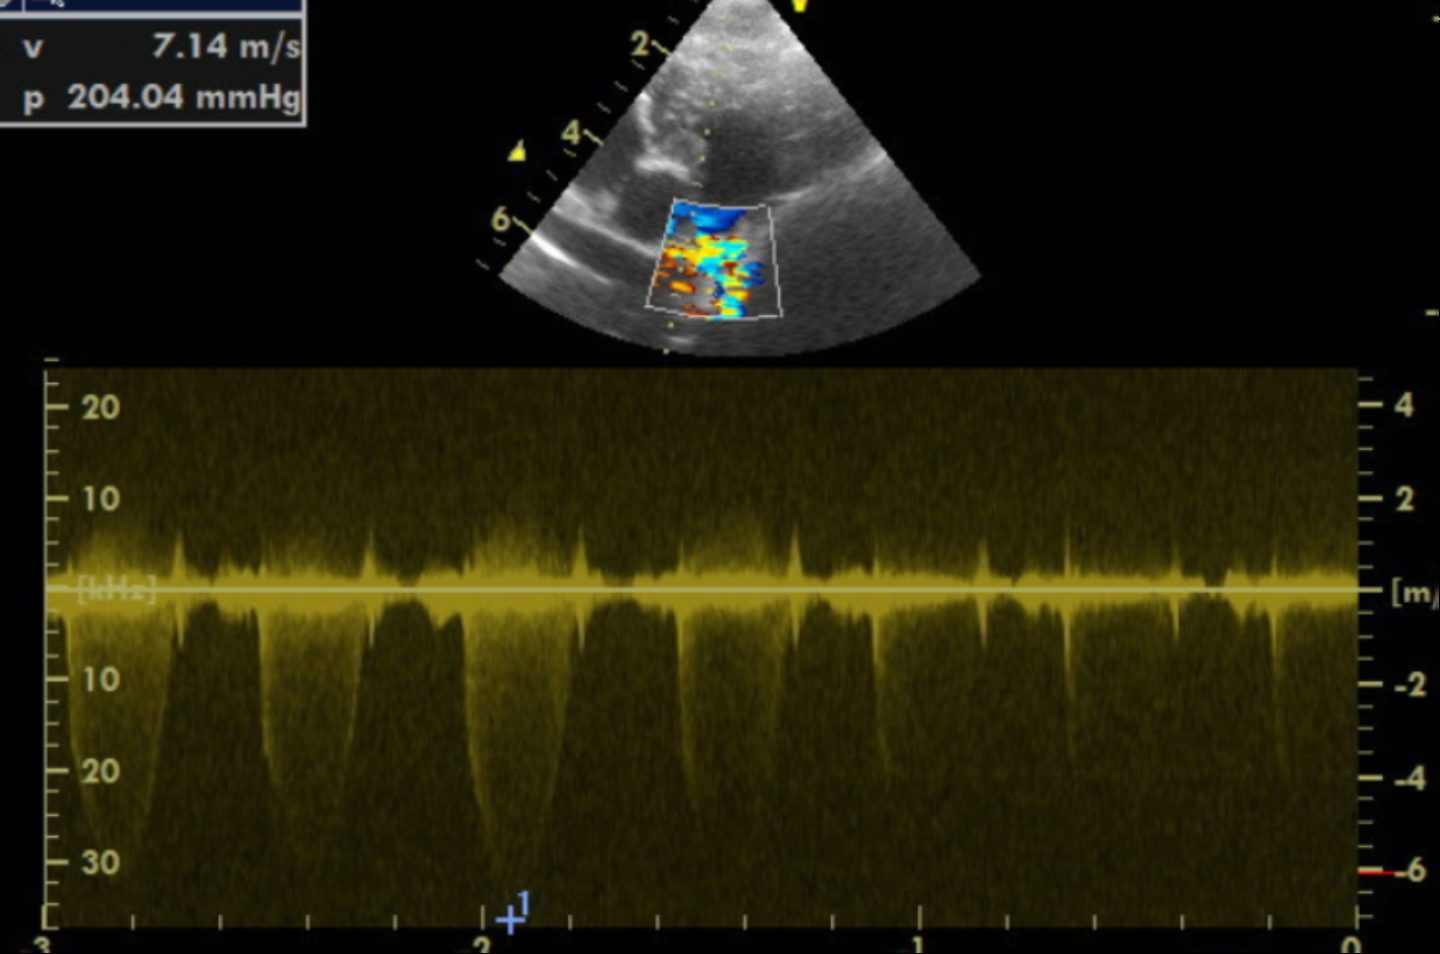

Im Herzultraschall zeigte sich eine hochgradig verdickte Muskulatur der Kammerwände der rechten Hauptkammer aufgrund einer hochgradigen Druckerhöhung. Es offenbarten sich außerdem angeborene Veränderungen der Mitralklappen und der Trikuspidalklappen. Bei der Darstellung der Pulmonalarterie zeigte sich eine missgebildete Pulmonalklappe, die wenig beweglich war. Zudem schloss und öffnete sie sich nicht vollständig. Die hochgradige Verwachsung der Pulmonalklappenöffnung führte zu einem sehr starken Anstieg des Blutdrucks von normalerweise 20 mmHg (Millimeter Quecksilbersäule) auf über 200 in der rechten Hauptkammer. Außerdem war der Klappenring der Pulmonalarterie sehr eng angelegt, wodurch der Schweregrad zusätzlich negativ beeinflusst wurde.

Bei Gonzo konnte der hochgradige Druckgradient von initial über 200 mmHg um mehr als 50 % auf 75 mmHg gesenkt werden. Dies stellt einen überaus erfolgreichen Verlauf des Eingriffes dar. Gonzos Druckgradient in der rechten Hauptkammer konnte vom hochgradigen Bereich erfolgreich auf einen mittelgradig erhöhten Druckgradienten gesenkt werden! Dies bedeutet für Gonzo, dass durch den Eingriff, der minimalinvasiv und ohne Eröffnung des Brustkorbs erfolgte, eine normale Lebenserwartung mit normaler Lebensqualität erzielt werden konnte. Der interventionelle Eingriff hat sich für Gonzo und seine Besitzer gelohnt! Fünf Jahre später geht es Gonzo nach wie vor sehr gut.

Je höher der Druck in der rechten Kammer ist, desto hochgradiger wird die Verdickung der Muskulatur im rechten Herzen. Symptome können Schwäche, Synkopen (Ohnmachtsanfälle) oder ein Rechtsherzversagen sein (wie im Falle von Gonzo, der dadurch eine hochgradige Bauchwassersucht entwickelte). Während leicht bis mittelgradig betroffene Patienten eine normale Lebenserwartung haben, erwartet hochgradige Patienten ohne Eingriff in der Regel ein vorzeitiges Ableben. Dabei zählt bereits ein Druckgradient von 80mmHg als hochgradig. Gonzo hatte anfangs einen Druckgradienten von über 200 mmHg! Eine Absenkung durch den Eingriff auf 75 mmHg spricht für einen absolut erfolgreichen Eingriff.